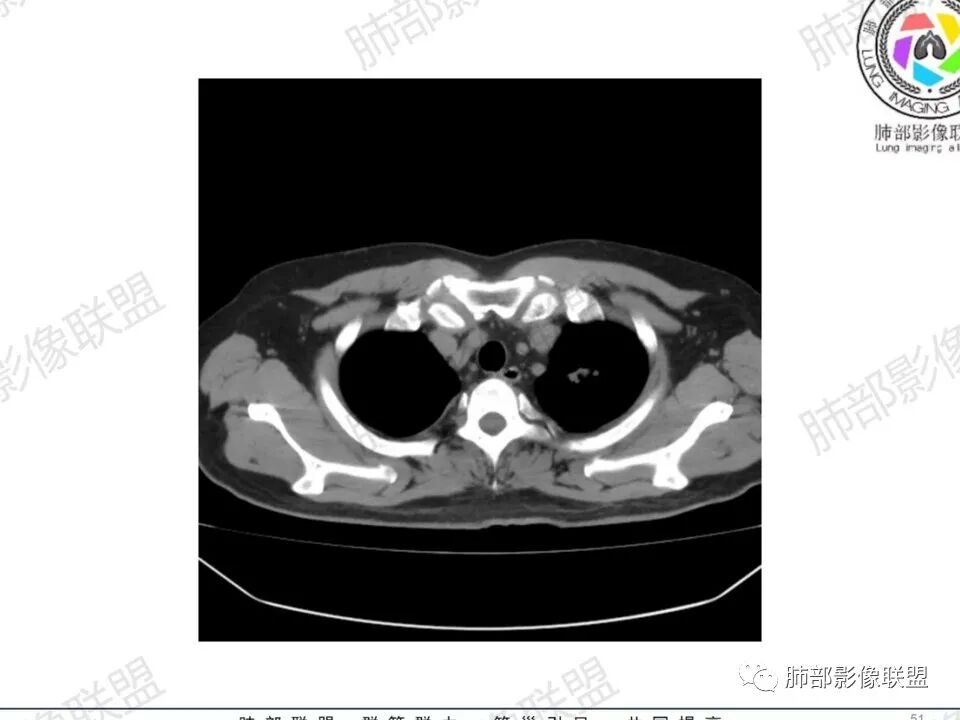

双肺多发结节,胸膜下为主,部分可见空洞。左肺上叶尖后段结节较大,分叶毛刺,周围可见长条索及小斑片影,内空洞比较光滑,内侧壁可见支气管通过。右肺下叶后基底段不张实变,后侧积液,右侧水平裂积液,右侧膈胸膜纵膈胸膜增厚积液,右侧侧胸膜肥厚,考虑1:一元金葡。2二元:金葡,左肺上叶结核。

男,45岁,左手指红肿疼痛两天,右侧胸壁疼痛伴发热12小时入院。患者急性起病,胸部CT示双肺多发结节,部分伴空洞,空洞壁较光滑,右侧胸腔积液,考虑感染性病变,金葡菌加SPE可能

@赵永兵 内蒙巴市临河妇幼影像科 支气管是从旁边经过,所以不是空洞,是胸膜下的脓毒栓。如果是结核空洞,应该与支气管相通(因为结核没有血播感染表现的时候,来源是气道,空洞应该与支气管相通),所以支气管从旁边经过,这病灶又在胸膜下,周围也没有干酪坏死。当然是SPE了。

中年男性,左手中指及胸壁疼痛伴发热来诊,影像见双肺多发结节,胸膜下分布为主,部分结节可见空洞,边缘模糊。左肺上叶尖后段结节较大。右肺下叶后基底段不张实变,右侧叶间裂及右侧胸腔积液,右侧侧胸膜肥厚。考虑金葡菌感染,血播SPE。

空洞内壁光滑,偏心厚壁空洞,张力高